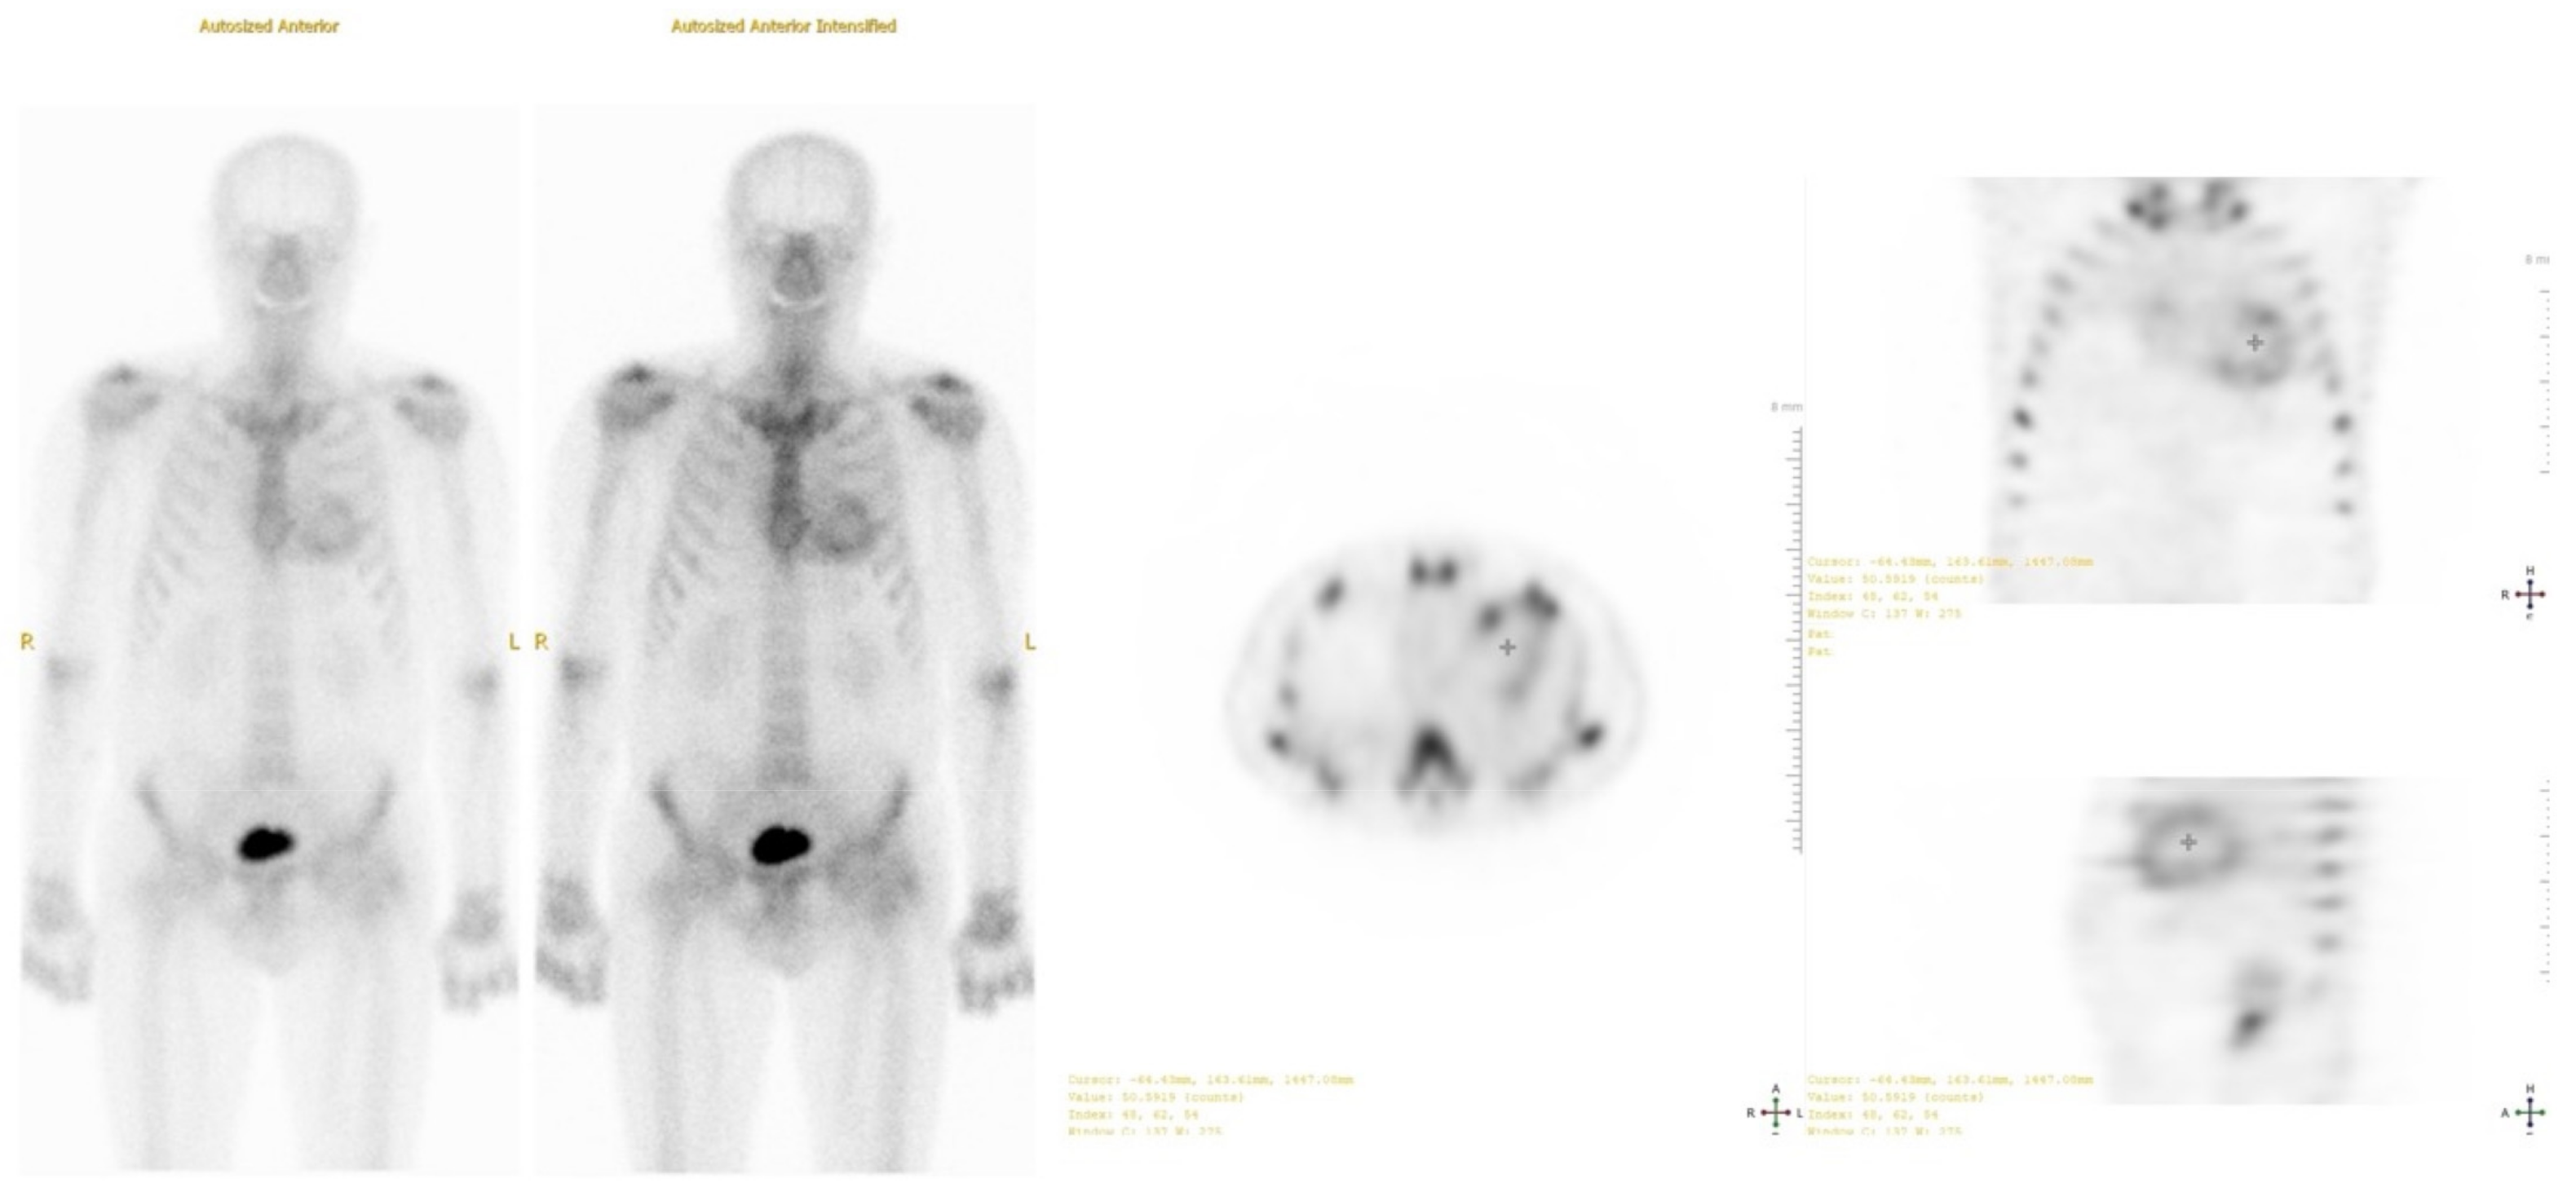

To confirm the presence and type of amyloidosis, technetium-99m pyrophosphate scintigraphy and single photon emission computed tomography (SPECT) were performed (Figure 5). The results obtained using the qualitative assessment scale corresponded to degree 3 (Perugini scale). A genetic test showed no mutations in the TTR gene. Based on these findings, wild-type transthyretin cardiac amyloidosis was diagnosed.

Figure 5.

Technetium-99 m pyrophosphate single photon emission computed tomography (SPECT): positive uptake of radiotracer in the heart 1 h after injection (Grade 3).